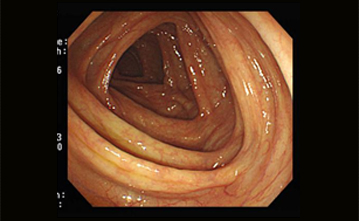

잘된 사항

잘못된 경우 - 검사불량